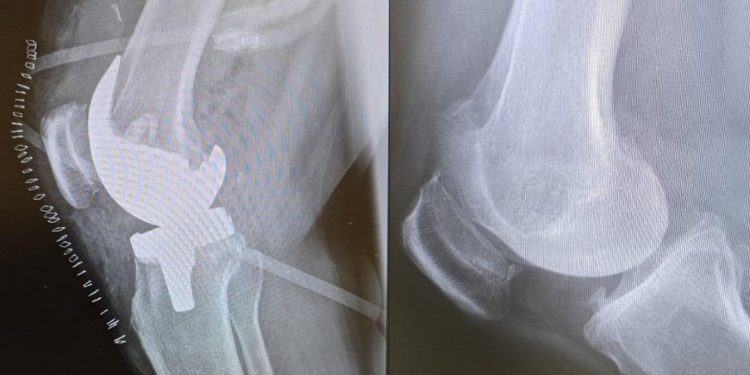

تمكن الفريق الطبي في مستشفى الدكتور سليمان الحبيب بالمحمدية – جدة، من إجراء عملية دقيقة لاستبدال مفصلي الركبة لسيدة تبلغ من العمر 67 عامًا، كانت تعاني من خشونة شديدة من الدرجة الرابعة، أدت إلى ألم حاد وانتفاخ في الركبتين وصعوبة كبيرة في الحركة.

وبعد تقييم الحالة، تم اتخاذ قرار بإجراء عملية جراحية عاجلة، حيث خضعت المريضة لعملية استمرت ثلاث ساعات ونصف، تم خلالها استبدال المفصلين بمفاصل صناعية متطورة من مادة الكوبالت كروم، والتي تُعد من أكثر الأنواع كفاءة ودوامًا عالميًا.